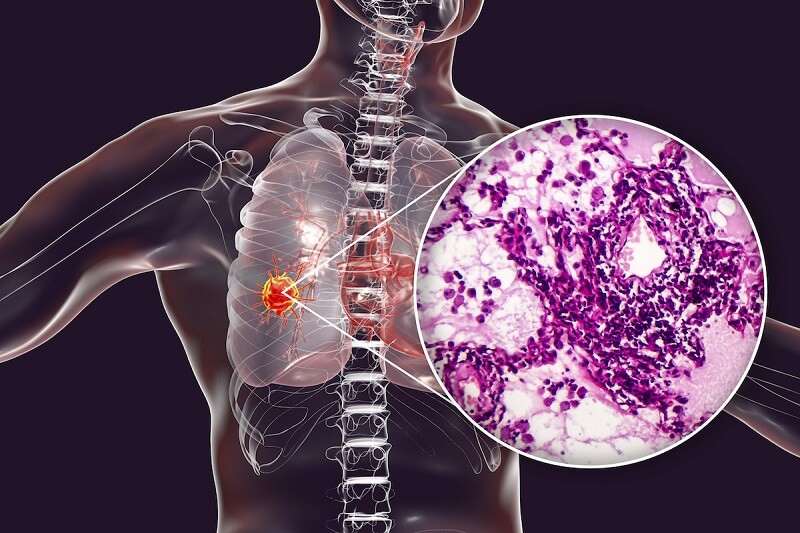

Giải phẫu bệnh được tiến hành trên mẫu bệnh phẩm là tế bào hay mô của những cơ quan bên trong cơ thể, sinh thiết qua các quá trình như phẫu thuật, nội soi, ... Có thể coi giải phẫu bệnh là một tiêu chuẩn vàng để chẩn đoán bệnh chính xác, kịp thời, nhất là đối với những bệnh lý ác tính. Với nhiệm vụ quan trọng cần gánh vác, cán bộ y tế hoạt động trong mảng này cần nắm rõ giải phẫu bệnh là gì. Bài viết dưới đây sẽ hỗ trợ bạn khám phá rõ hơn về giải phẫu bệnh.

Giải phẫu bệnh là một xét nghiệm quan trọng, cũng là tiêu chuẩn vàng giúp chẩn đoán bệnh chính xác, nhất là những căn bệnh hiểm nghèo, ác tính. Từ đó, kết quả giải phẫu sẽ được lấy để làm cơ sở giúp bác sĩ xây dựng phác đồ điều trị hiệu quả.

Khái niệm giải phẫu bệnh là gì cũng hé mở cho chúng ta biết rằng phương pháp này có ứng dụng rất lớn, rất quan trọng trong việc chẩn đoán bệnh tật. Nói một cách cụ thể thì xét nghiệm giải phẫu bệnh được ứng dụng phổ biến trong nền y học nhằm đem đến những lợi ích sau đây:

- Sàng lọc và sớm phát hiện những trường hợp mắc bệnh ác tính

- Tiên lượng về những khối u ác tính và giai đoạn đang phát triển của khối u